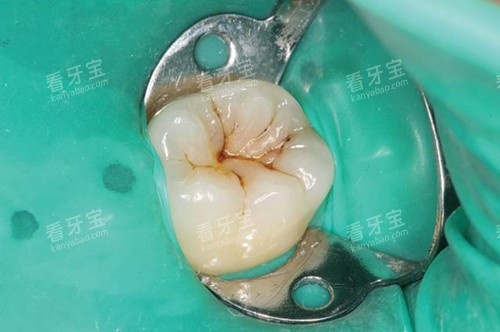

补牙:进口树脂补牙298元起,树脂补牙约300元起/颗,补牙202元起。